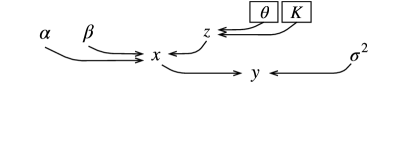

Fig. 1 illustrates the hierarchical model used to perform a joint deconvolution-segmentation of ultrasound images. The following likelihood function is derived from (1)